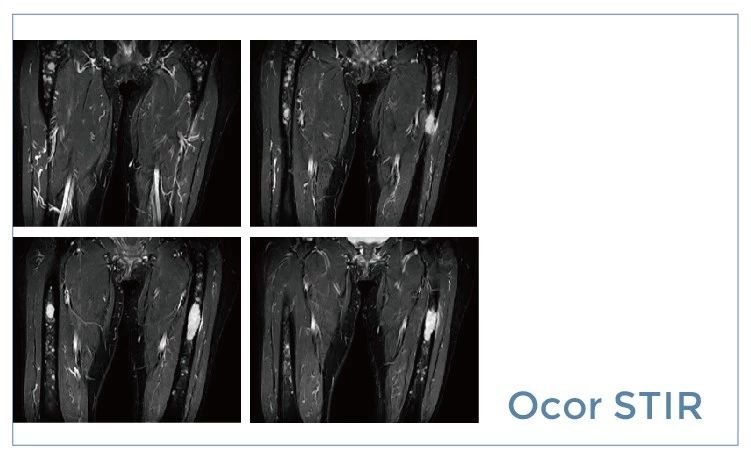

【朗润影像档案】20190712磁共振影像病例结果讨论